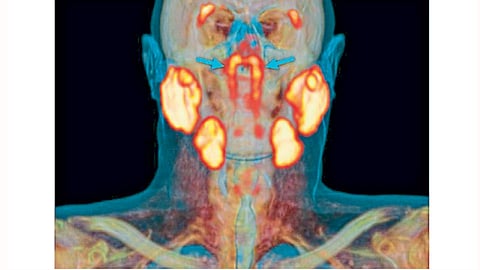

पीएसएमए पेट/सीटी या अत्याधुनिक यंत्राव्दारे कर्करोगाच्या एका रुग्णाचे स्कॅनिंग करत असताना नेदरलँडमधील डॉक्टरांना या नवा अवयवाचा शोध लागला. कर्करोगाच्या गाठी समजण्यासाठी हे स्कॅनिंग करण्यापूर्वी रुग्णाला किरणोत्सारी द्रव असलेले ग्लुकोजचे इंजेक्शन दिले जाते. त्यामुळे कर्करोगाच्या गाठी स्कॅनमध्ये ‘उजळलेल्या’ दिसतात. या स्कॅनमध्ये नासोफरीनॅक्स भागात (मृदूटाळूवरील भाग) आत्तापर्यंत कधीही न दिसलेला भाग दिसून आला. मुख्य लाळग्रंथीच्या बाजूला या दोन नव्या ग्रंथी असल्याचे दिसून आले.

पचनासाठी आपल्याला लाळेची गरज असते. पॅराटॉईड, सबमँडीब्युलर आणि सबलिंग्युलर या ग्रंथींमधून लाळ स्रवते. याशिवाय लाळ स्रवणाऱ्या छोट्या छोट्या हजारभर ग्रंथीही असतात. त्या सर्व आपल्या तोंडामध्ये विखुरलेल्या असतात. सूक्ष्मदर्शकाशिवाय या छोट्या-छोट्या ग्रंथी दिसत नाहीत. नव्याने सापडलेल्या ठळकपणे दिसणाऱ्या चौथ्या ग्रंथी आहेत. नाकाच्या मागे आणि टाळूच्या वरच्या भागात, मानवी डोक्याच्या मध्याच्या जवळ आहेत.

ॲमस्टरडॅम विद्यापीठातील शल्यचिकित्सक मॅथिज वॉल्स्टार यांच्या नेतृत्वाखालील पथकाने या नव्या ग्रंथींचा अभ्यास केला. नव्या अवयाबाबत ते म्हणाले,` या ग्रंथींच्या स्थानावरून त्यांना ट्युबेरिअल ग्लँड असे त्यांना म्हणता येऊ शकेल. या साठी १०० रुग्णांची तपासणी करण्यात आली. त्या सर्वांचे पीएसएमए पेट/सीटी स्कॅन करण्यात आले. सर्वांमध्ये या नव्या ग्रंथी आढळून आल्या. तसेच एक महिला व एका पुरुषाची प्रत्यक्ष शारीरिक तपासणी करण्यात आली त्यातही या पेशी आढळून आल्या. आतापर्यंतच्या वैद्यकीय पाहणीत या ग्रंथी आढळून आल्या नव्हत्या.``